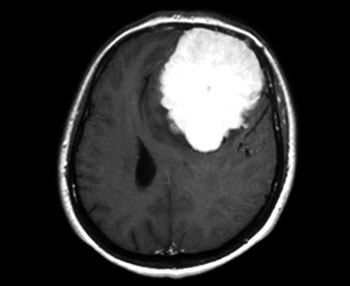

Ο υπερηχογραφικός έλεγχος του εμβρύου δείχνει μονήρη κύηση με φυσιολογική ανάπτυξη του εμβρύου και με αυτόν αποκλείονται παθολογικές καταστάσεις όπως υδράμνιο, εμβρυϊκός ύδρωπας και αποκόλληση του πλακούντα. Το υπερηχογράφημα της άνω κοιλίας και των νεφρών Π ουρητήρων - κύστης είναι χωρίς παθολογικά ευρήματα. H βυθοσκόπηση δείχνει οίδημα και ασαφή όρια των οπτικών θηλών. Στη μαγνητική τομογραφία εγκεφάλου ανευρίσκεται ευμεγέθης χωροκατακτητική εξεργασία στη μετωποβρεγματική περιοχή αριστερά, με σαφή όρια και διαστάσεις 8,5x7x5 εκ. (εικόνα 1). Ο όγκος προκαλεί παρεκτόπιση της μέσης γραμμής ετερόπλευρα, συμπίεση και παραμόρφωση της αριστερής πλάγιας κοιλίας, εγκολεασμό του αριστερού μετωπιαίου λοβού υπό το δρέπανο και περιεστιακό οίδημα - ευρήματα συμβατά με μηνιγγίωμα.

Εικόνα 1

Εικόνα 1. Μαγνητική τομογραφία εγκεφάλου που απεικονίζει ευμεγέθη χωροκατακτητική εξεργασία η οποία προκαλεί παρεκτόπιση της μέσης γραμμής με συμπίεση και παραμόρφωση της αριστερής πλάγιας κοιλίας.